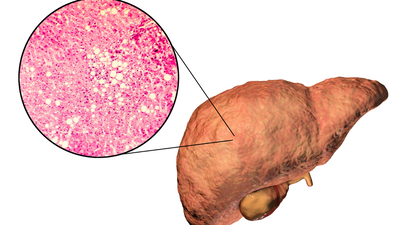

फैटी लीवर रोग एक प्रकार का सार्वजनिक स्वास्थ्य संकट है जिससे केवल कुछ ही लोग बच पाएंगे। हेपेटोलॉजी जर्नल में प्रकाशित एक व्यवस्थित समीक्षा के आधार पर, अब लगभग 38% वयस्कों को गैर-अल्कोहलिक फैटी लीवर रोग (एनएएफएलडी) होने का अनुमान है।फैटी लीवर का निदान, जैसा कि हम में से अधिकांश लोग सोचते हैं, केवल लीवर में वसा का संचय है, लेकिन हमें आश्चर्य है कि यह साधारण वसा के निर्माण से कहीं अधिक है। कार्यात्मक चिकित्सा विशेषज्ञ डॉ. रॉबर्ट डीबीज़ का कहना है कि यह उससे कहीं अधिक जटिल है। उनकी राय में, फैटी लीवर का मुद्दा आपके शरीर के भीतर पोषक तत्वों के साथ क्या हो रहा है, और विशेष रूप से तांबे, विटामिन ए और यहां तक कि फलों में चीनी की ओर इशारा करता है।

सबसे पहले, आइए फैटी लीवर की सरल अवधारणा पर पुनर्विचार करें। डॉ. डीबीज़ बताते हैं कि इस स्थिति का होना वसा के बारे में इतना अधिक नहीं है। बल्कि, “छिपे हुए ट्रिगर्स”, और ये तांबा, विटामिन ए, और फल शर्करा (फ्रुक्टोज़) हैं। लीवर, विष को छानने वाला अंग है, और इसकी मुख्य जिम्मेदारी आयरन को लीवर से बाहर निकालकर रक्त में रखना है, जिससे शरीर गतिमान रहता है।यहीं पर बात भ्रमित करने वाली हो जाती है। यदि आपके पास पर्याप्त तांबा या विटामिन ए नहीं है, तो वह आयरन लीवर में रुक जाता है। लोहे को एक ट्रक के रूप में कल्पना करें जो गोदाम से बाहर नहीं जा सकता। यह इन्वेंट्री लीवर कोशिकाओं को नष्ट करना शुरू कर देती है और वसा जमा करना शुरू कर देती है। तो, आपके लीवर को सहारा देने में, यह केवल कम वसा का उपभोग करने के बारे में नहीं है – यह इस आयरन-शंटलिंग प्रक्रिया को ठीक से काम करने में सहायता करने के बारे में है।

दूसरा, फलों में शर्करा पाई जाती है, जिसे फ्रुक्टोज के नाम से जाना जाता है। कोई सोच सकता है कि फल हर समय स्वास्थ्यवर्धक होते हैं, लेकिन डॉ. डीबीज फैटी लीवर वाले लोगों के लिए एक चेतावनी साझा करते हैं। वह आहार से फलों को पूरी तरह से हटाने की सलाह देते हैं और इसका कारण यह है कि फ्रुक्टोज प्राथमिक रूप से यकृत द्वारा चयापचय किया जाता है और चयापचय में बहुत अधिक ऊर्जा का उपयोग होता है। यदि हम अधिक फ्रुक्टोज का सेवन करते हैं, तो लीवर पर अधिक भार पड़ जाता है और वह “जलने” लगता है।समय के साथ लीवर की कोशिकाएं क्षतिग्रस्त हो जाती हैं, खासकर अगर शरीर में कॉपर और विटामिन ए का स्तर पहले से ही कम हो। यह एक लगातार समस्या पैदा करता है, जिससे फैटी लीवर रोग का चक्र बना रहता है।डॉ. डीबीज़ न केवल समग्र रूप से कार्ब्स को कम करने की सलाह देते हैं, बल्कि विशेष रूप से फलों से मिलने वाली शर्करा से भी परहेज करते हैं। फैटी लीवर वाले व्यक्ति के लिए, फल उतना हानिरहित नहीं लगता जितना दिखता है।यहाँ एक और स्तर है. कॉपर और विटामिन ए शरीर के अंदर उसी तरह से सहयोग करते हैं जैसे हमारे कार्य और दिमाग करते हैं। वे आयरन को लीवर से रक्त में स्थानांतरित करने में सहायता करते हैं। यदि ये पोषक तत्व पर्याप्त मात्रा में नहीं हैं, तो संपूर्ण प्रणाली ध्वस्त हो जाती है। आयरन चिपक जाता है और परिणामस्वरूप, लीवर कोशिकाएं घायल हो जाती हैं और वसा जमा होने लगती है।